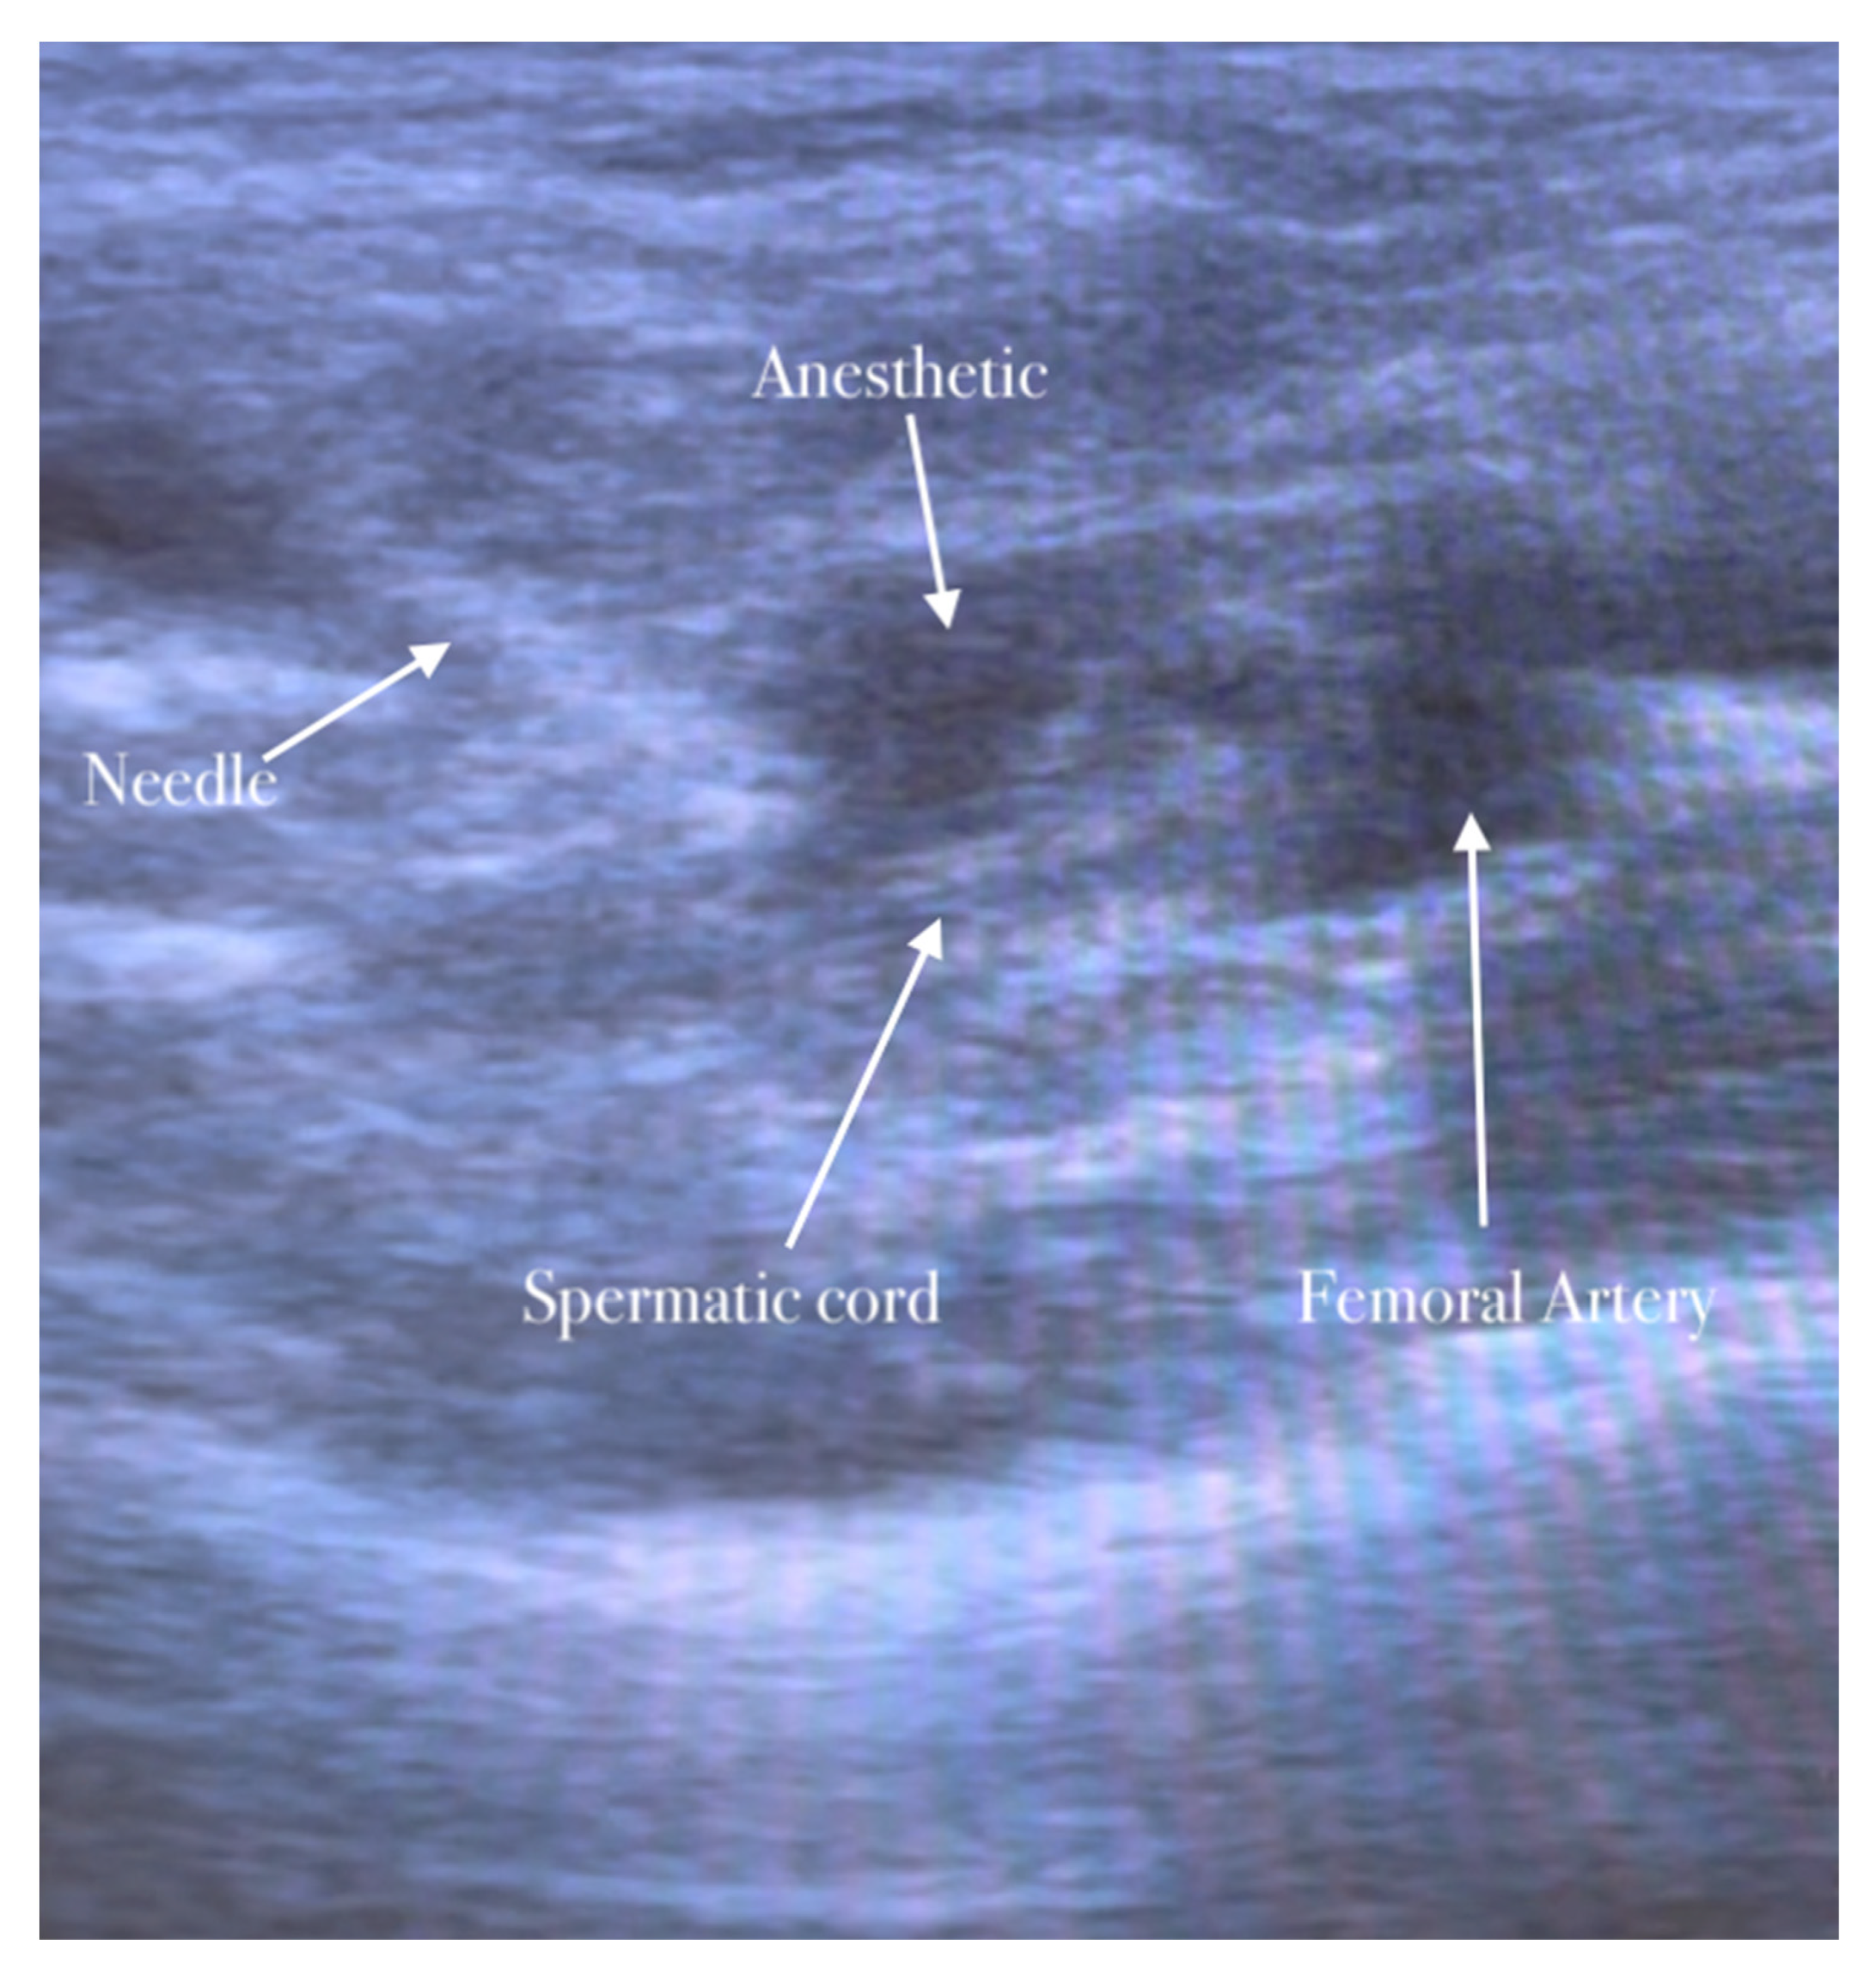

The second step of anesthesia consists of the genitofemoral nerve block. The genitofemoral nerve block decreases the pain induced by the traction of the hernia sac and improves the quality of analgesia for surgery in the inguinal region. The procedure is similar to the ilioinguinal–iliohypogastric nerves block. The genitofemoral nerve is formed from the first and second ventral rami of the lumbar nerve. It emerges on the anterior surface of the psoas major along the medial border, descends on the psoas major within the fascia iliaca, and crosses the posterior to the ureter and peritoneum. The nerve follows the lateral border of the common and external iliac artery. It is divided into genital and femoral branches above the inguinal ligament. The genital branch of the genitofemoral nerve passes through the transversalis and spermatic fascia before it enters the deep inguinal ring. It lies immediately laterally or deeply in the spermatic cord/round ligament and supplies the cremaster muscle [16,17].

The high-frequency linear probe is initially kept perpendicular to the inguinal ligament just above the femoral vessels. The final position of the probe is about 2 cm lateral to the pubic tubercle. In this position, the femoral artery is identified. The inguinal canal lies above and medially the femoral artery appearing as an oval or circular structure. The probe is then moved slightly in the medial direction away from the femoral artery.

The needle is inserted in the plane in a medial-to-lateral direction; 10 mL of anesthetic is injected in the transversus abdominis plane, as seen in Figure 5, Figure 6 and Figure 7.

The anesthetic is injected in the spermatic cord.